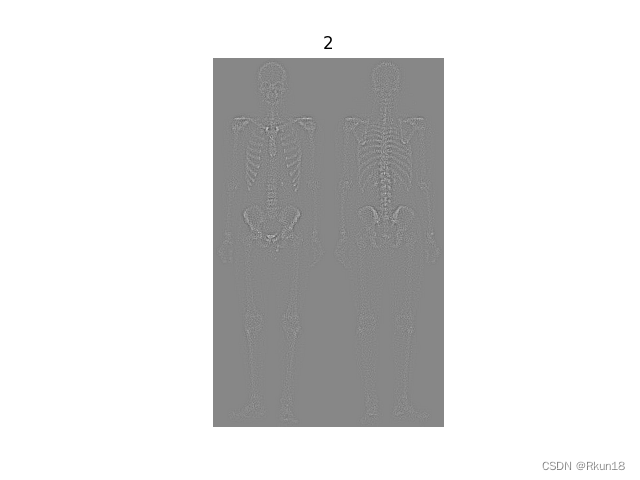

2:1拉普拉斯变化后:

图像全身骨骼扫描,图2为原始图像拉普拉斯变换后的结果,细节信息丰富,同时噪音变多。

上图更能直观地观察到图像变换后的差异。

文章介绍了混合图像增强技术在处理人体骨骼扫描图像中的应用,包括使用拉普拉斯变换增强细节,Sobel算子突出边缘,以及灰度幂律变换优化图像对比度。通过一系列图像处理步骤,实现了在保持细节的同时减少噪声并增强图像清晰度。